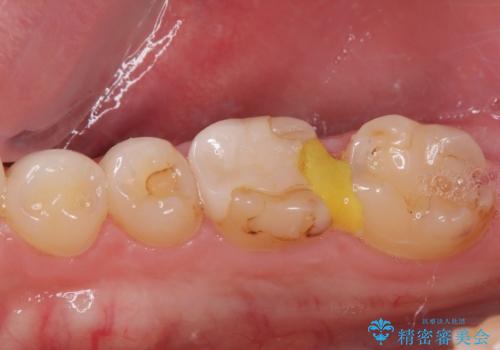

拡大鏡視野下で、セラミックの詰め物(セラミックインレー)、虫歯の除去を行い、オールセラミッククラウンに適した形に整えました。

歯と歯茎の間に圧排糸と言われる糸を入れてシリコーン印象材にて型どりをしました。